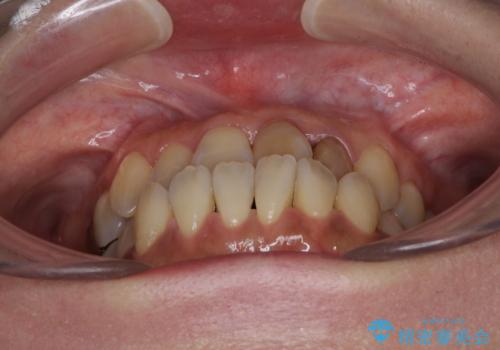

- 前歯の反対咬合により、日々強い痛みを感じているとのことで来院された患者様です。

骨格的に下顎が前方位にありますが、歯列矯正で前歯の被蓋関係を改善することができると判断されたため、インビザラインにより矯正治療を行うこととしました。

また、上顎前歯と下顎大臼歯に神経を取り除いた歯があったため、矯正治療後に、セラミッククラウンにて補綴することとしました。

前歯が内側に倒れ込む力がかかり、正常な歯ぎしりもできないため、非常に負担のかかりやすい咬み合わせでした。

矯正治療中に上顎前歯が下顎前歯を乗り越える際は、前歯でしか咬めない状況が続くため、食事など不便を感じましたが、治療後には前歯の痛みもなくなり、安定した咬み合わせとなりました。